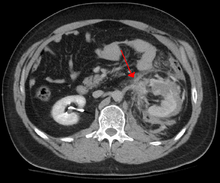

In all but the most obviously trivial injuries, the first concern is to exclude anything that might be quickly or immediately life-threatening. This is resolved by ascertaining that the subject's airway is open and competent, that breathing is unlabored, and that circulation — i.e. pulses that can be felt, is present. This is sometimes described as the "A, B, C's" — Airway, Breathing, and Circulation – and is the first step in any resuscitation or triage. Then, the history of the accident or injury is amplified with any medical, dietary (timing of last oral intake) and past history, from whatever sources such as family, friends, previous treating physicians that might be available. This method is sometimes given the mnemonic "SAMPLE". The amount of time spent on diagnosis should be minimized and expedited by a combination of clinical assessment and appropriate use of technology,[6] such as diagnostic peritoneal lavage (DPL), or bedside ultrasound examination (FAST)[7] before proceeding to laparotomy if required. If time and the patient's stability permits, CT examination may be carried out if available.[8] Its advantages include superior definition of the injury, leading to grading of the injury and sometimes the confidence to avoid or postpone surgery. Its disadvantages include the time taken to acquire images, although this gets shorter with each generation of scanners, and the removal of the patient from the immediate view of the emergency or surgical staff.